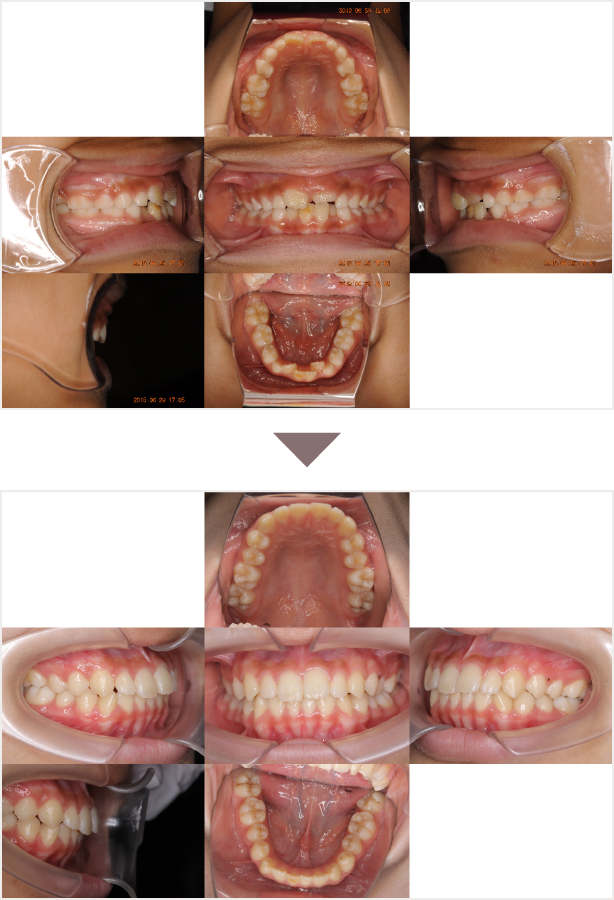

症例交差咬合

性別

期間3年8ヶ月

治療内容N-Bimler装置、Neo-Capを使用して治療

治療における

副作用・リスク

装着しないと効果は出ません

金額ビムラー装置:550,000円

ネオキャップ:8本

合計:594,000円